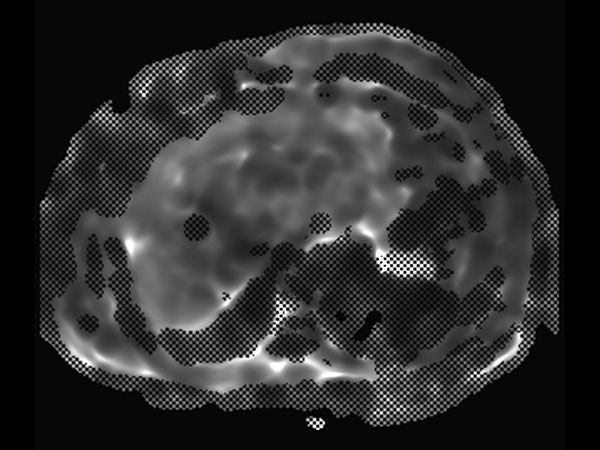

mDIXON Quant (T2 star)